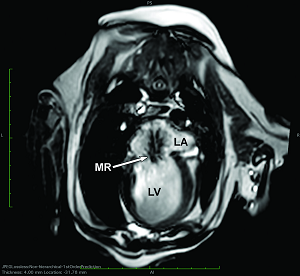

Mitral valve leaflets

MVD is a degeneration and fibrosis of the heart's mitral valve, one of

four sets of valves in a canine's (and a human's) heart. It is the valve

which is designed to prevent the backflow of blood from the left ventricle

into

the left atrium (called mitral regurgitation -- MR).

Eventually, the leaflets no longer fully close after each pumping action, allowing blood to jet backwards through them from the ventricle back into the atrium. This is the mitral regurgition (MR). (In the diagram at the upper left, a healthy mitral valve at the top is compared with a damaged valve below.)